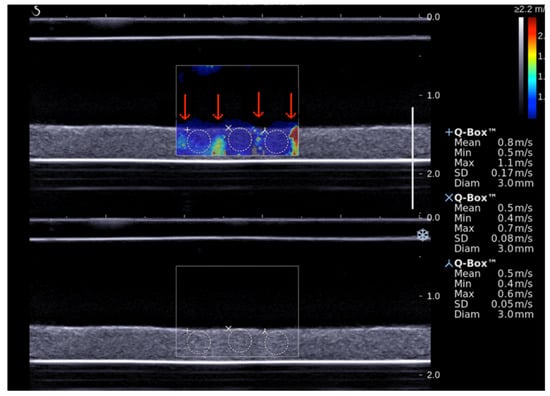

2.6. Shear Wave Elastography Imaging

3.2. Assessment of SWS during Sonothrombolysis